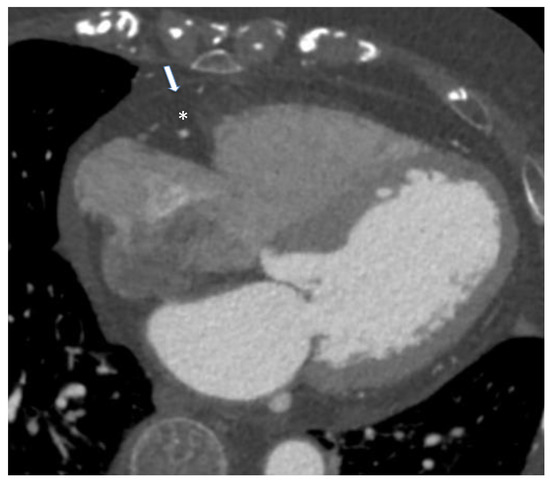

Nowadays, no globally accepted cut-off to define normal and pathological values for CT-derived EAT measures is defended. Spearman et al. reported an EAT volume above 125 mL as an indicator of cardiac pathology [44]. Other investigators have shown even that an EAT threshold between 113 and 120 cm3 has the greatest predictive value for future cardiovascular events [41,44]. CT allows the quantification of EAT X-ray radiodensity, which may be a biomarker of its metabolic activity, possibly related to cardiovascular or metabolic diseases [45]. Vascular inflammation localized in the coronary arteries leads to an increased risk of coronary artery disease (CAD)-related events and produces biological alterations to local cardiac adipose tissue depots. Coronary CT provides information on inflammatory changes to both EAT and PCAT, as independent markers of coronary risk. Attenuation of PCAT on CT provides indirect quantification of coronary inflammation and could be emerging as a promising imaging implement in both stable and “vulnerable” populations. While standardized CT thresholds of inflammation are yet to be established, they present a powerful avenue to enhance primary prevention initiatives [10]. A new biomarker called “fat attenuation index (FAI)”, defined as the mean PCAT attenuation within a radial distance from the outer coronary artery wall equal to the average vessel diameter, was proposed. It was higher in patients with CAD than those without CAD and was associated with coronary stenosis greater than 50%. The presence of inflammation results, in fact, in smaller pre-adipocytes with less intracellular lipid, causing an increase in PCAT attenuation [46] (Figure 4).

Figure 4.

Case of an 85-year-old male patient underwent cardiac computed tomography angiography for the evaluation of coronary artery disease. Arrow identifies pericardium while asterisk represent epicardial adipose tissue. From Giuseppe Muscogiuri’s private archive of unpublished cardiac imaging.